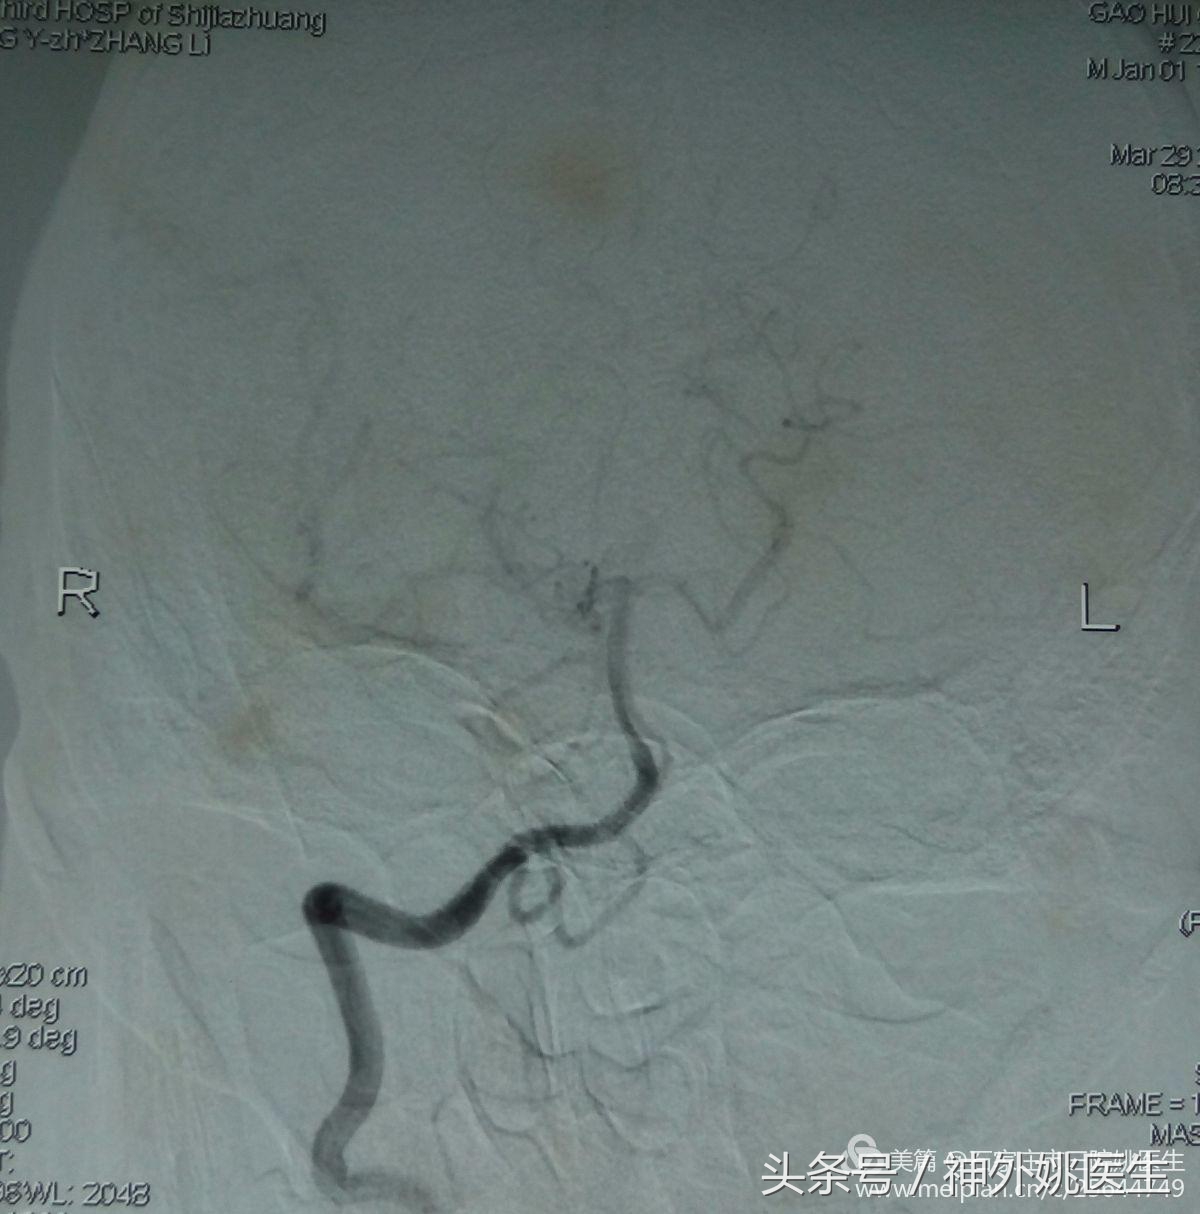

2.右颈内动脉颅内段造影示:右大脑前动脉不显(图9)。

图(9)

4.左颈内动脉颅内段造影示:左侧大脑前动脉A1段供应双侧A2,前交通动脉开放(图11)。

(图11)

5.椎动脉颅内段造影示:右侧大脑中动脉供血区显影,提示后交通动脉开放(图12)。

(图12)